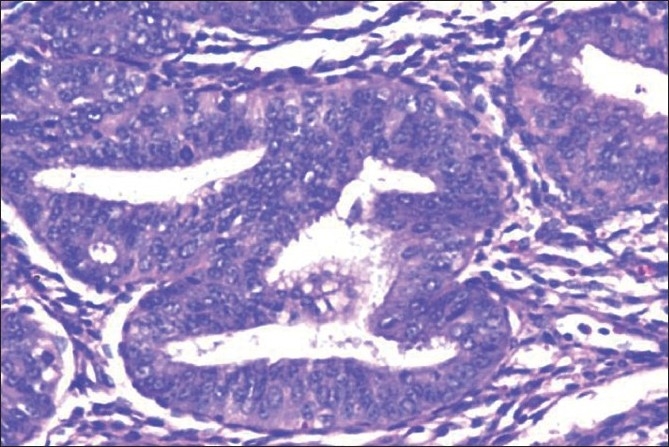

A total of 1778 cases of endometrial hyperplasia / polyp / carcinoma were studied. Out of these only 74 patients with endometrial hyperplasia and five cases of benign endometrial polyps came for subsequent follow-up. Patient with endometrial hyperplasia under follow up included 59 cases of SH [Figure 1], 10 cases of CH, and five cases of CHA [Figure 2] at their first visit [Table 1]. The overall follow-up of the study cases showed progression, regression, and persistence of lesion [Table 2]. A varied pattern was seen on follow-up of each subtype of hyperplasia and endometrial polyp [Table 3].

| Figure 2 Closely packed endometrial glands with sparse intervening stroma and stratification of the lining epithelium. Epithelial cells show cytological atypia with high nucleocytoplasmic ratio, irregular clumping of nuclear chromatin, and mitotic figures (Hematoxylin and eosin stain, ×200)